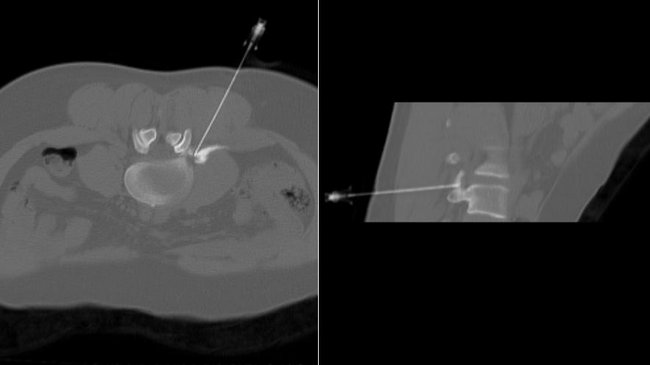

Bei verschleißbedingten Schmerzen der Wirbelsäule oder Bandscheibenproblemen können unter computertomographischer Kontrolle schmerz- und entzündungshemmende Medikamente zielgenau an die Schmerzquelle gebracht werden. Dadurch wird eine Schmerzlinderung über Wochen bis Monate erreicht.